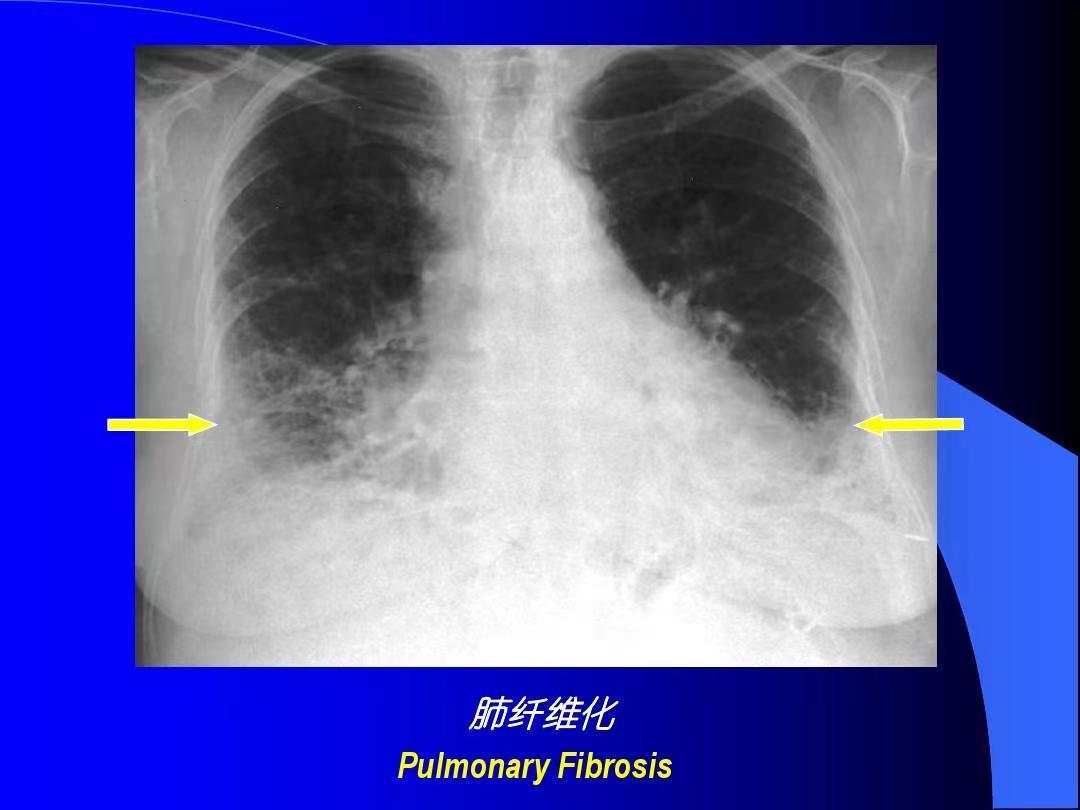

类风湿关节炎是一种自身免疫性炎性疾病,不仅会引起关节慢性疼痛,而且也会影响到其他的器官健康,最常见的就是影响肺部,很容易出现肺间质纤维化的问题,进而导致呼吸困难等不良的症状。

肺间质纤维化的病人往往会有顽固性的咳嗽和进行性的呼吸困难,会严重的影响生活质量。发现肺间质纤维化,首先要尽快的明确病因,这是因为纤维化是一大类异质性疾病,有的原因非常明确,比如有一类纤维化是跟吸烟相关,大家远离*草烟**不接触二手烟之后,病变会逐步的吸收,治疗主要是脱离环境,还有一些纤维化跟风湿免疫病相关,例如类风湿性关节炎、皮肌炎等,就需要很好地控制原发疾病,当原发疾病改善之后肺间质病变也会有吸收、会有改善,最难治疗的是特发性肺间质纤维化,这一类患者目前成熟的治疗药物比较少,目前常用包括尼达尼布、吡非尼酮药物。中医治疗也是非常好的选择,中药的汤药和中成药很多会有化痰散结、补肺益肾、纳气平喘的作用,很多肺间质纤维化的病人症状也会得到非常好的控制。肺间质纤维化病人的急性加重期,在这个过程中很多病人的病情会突然的进展导致呼吸衰竭,这种情况下要抗感染治疗,给予糖皮质激素的治疗抑制特异性的炎症的进展,同时有可能会使用呼吸机。